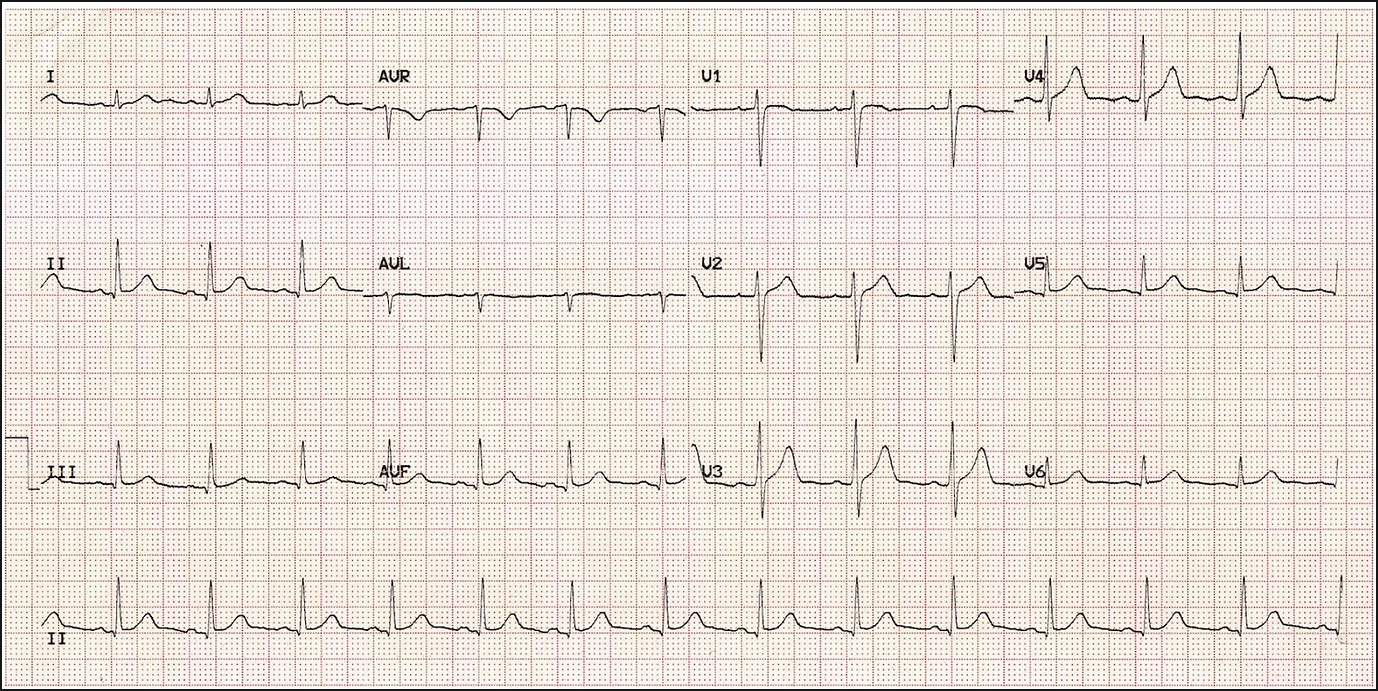

Lateral MI:

Here branches of the left anterior descending and left circumflex arteries have been affected.

There is ST elevation in the lateral leads (I, aVR V5 and V6).

There is reciprocal ST depression in the inferior leads III and aVF